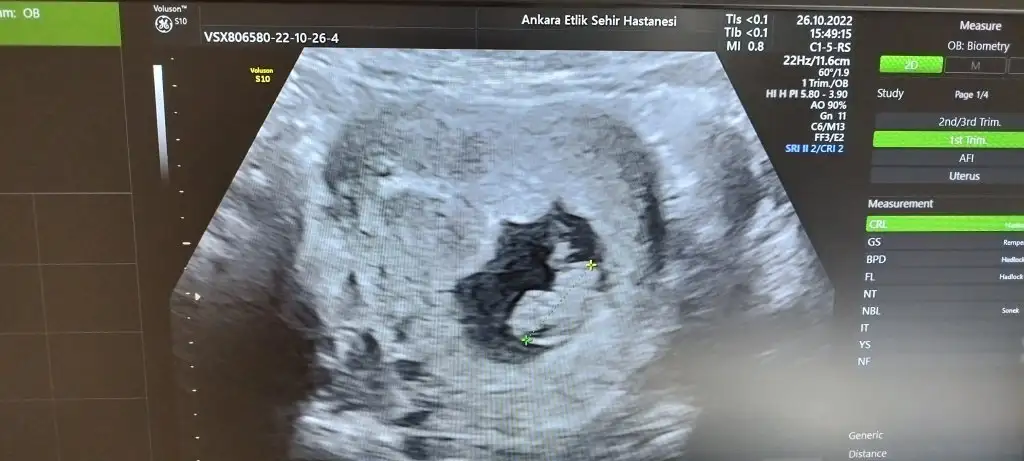

Kızlar 12+2 den merhaba bizde tahmin istiyoruzzz 🫶

• 3588652D-98B5-4025-87F9-DBBE0233345C.webp

3588652D-98B5-4025-87F9-DBBE0233345C.webp

19,5 KB · Görüntüleme: 37